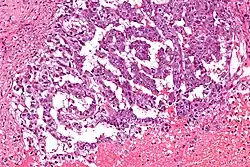

| Micrograph showing the yolk sac component of a mixed germ cell tumour. H&E stain. | |

EST can have a multitude of morphologic patterns including: reticular, endodermal sinus-like, microcystic, papillary, solid, glandular, alveolar, polyvesicular vitelline, enteric and hepatoid.

Schiller–Duval bodies on histology are pathognomonic and seen in the context of the endodermal sinus-like pattern. Rarely, it can be found in the vagina.[6][7]